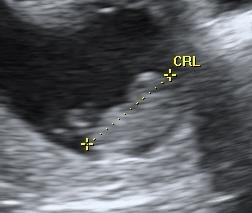

Så har vi igen været til scanning, og dte var bare en fantisk oplevelse, der var sket så meget på 2 uger, og den bette er vokset fint som den skal, der var både hjerteblink og hjertelyd, og endda lidt bevægelse, så det var bare helt perfekt, og enormt rørende

Ser nu frem til nakkefoldsscanning, og venter spændt på brev om hvornår vi skal derind